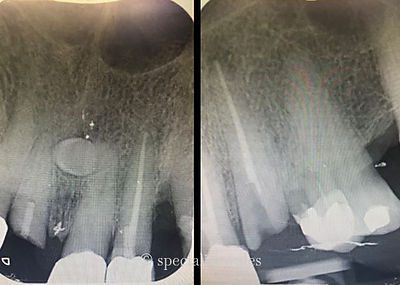

BEFORE

AFTER